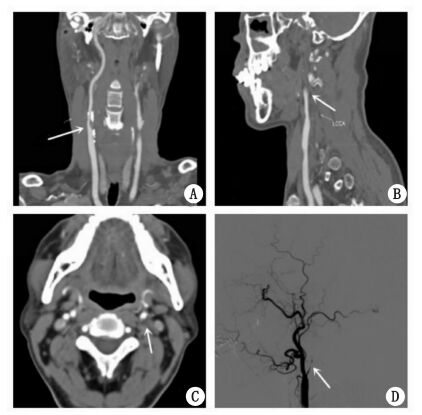

1 资料与方法患者男,62岁,既往有高血压病及高脂血症病史,均未正规治疗。1个月前因突发左侧肢体无力就诊当地医院。入院后急性查头颅CT诊断右侧基底节区脑梗死,同时颈动脉彩色多普勒超声显示右侧颈内动脉起始部重度狭窄,左侧颈内动脉闭塞。住院期间每日予阿司匹林片100 mg抗血小板聚集治疗,阿托伐他汀片10 mg降血脂稳定斑块以及控制血压等对症治疗,15 d后患者病情稳定出院。本次患者为行右颈内动脉支架植入术(CAS)于2014年8月就诊本院。入院时患者除遗留左侧肢体肌力减退(上肢肌力Ⅲ级,下肢肌力Ⅳ级)外,无明显阳性局灶性神经症状及体征。本院颈动脉CT血管造影(CTA)进一步证实右侧颈内动脉起始部重度粥样硬化性狭窄,狭窄率约90%(图 1A),左侧颈内动脉起始部闭塞(图 1B,1C)。头颅磁共振扫描显示右侧大脑基底节区新鲜脑梗死,左侧大脑半球实质未见缺血梗死灶。排除手术禁忌后,患者于入院第3天行经皮右侧颈内动脉支架植入术,术中DSA血管造影证实左侧颈内动脉完全闭塞(图 1D)。支架植入术过程顺利,术中共计使用普通肝素4 500 U。围手术期及术后患者均未出现手术相关并发症。术后3 d患者顺利出院。出院后患者每日口服阿司匹林片100 mg、氯吡格雷片75 mg抗血小板聚集治疗,阿托伐他汀片10 mg降血脂稳定斑块,同时给予口服降压药物降压治疗。

| 图 1 患者颈动脉支架植入术前颈动脉CTA(A、B、C)及术中左侧颈动脉DSA血管造影(D) |